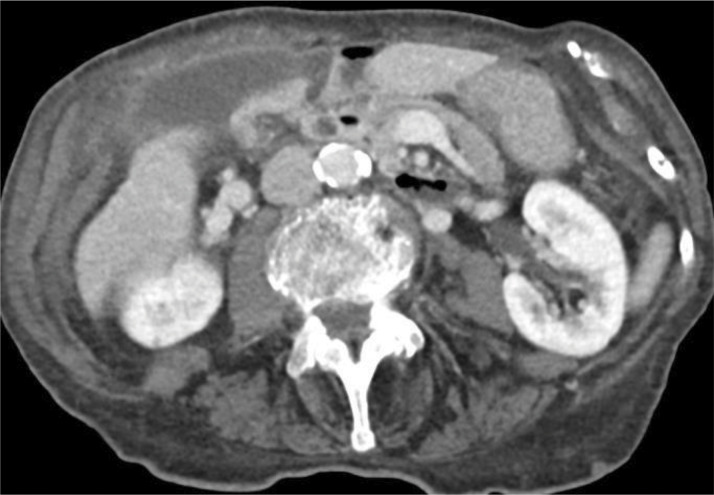

Teaching point: Gallbladder volvulus is a rare but serious diagnosis that needs urgent surgical treatment to avoid morbidity and mortality related to gallbladder ischemia and should be suspected in elderly female patients with acute right upper quadrant pain with imaging features including enlarged, abnormally positioned gallbladder and specific key findings on CT including "whirl sign" representing twisting of the cystic pedicle and "beak sign" at the gallbladder neck.

Abstract Image